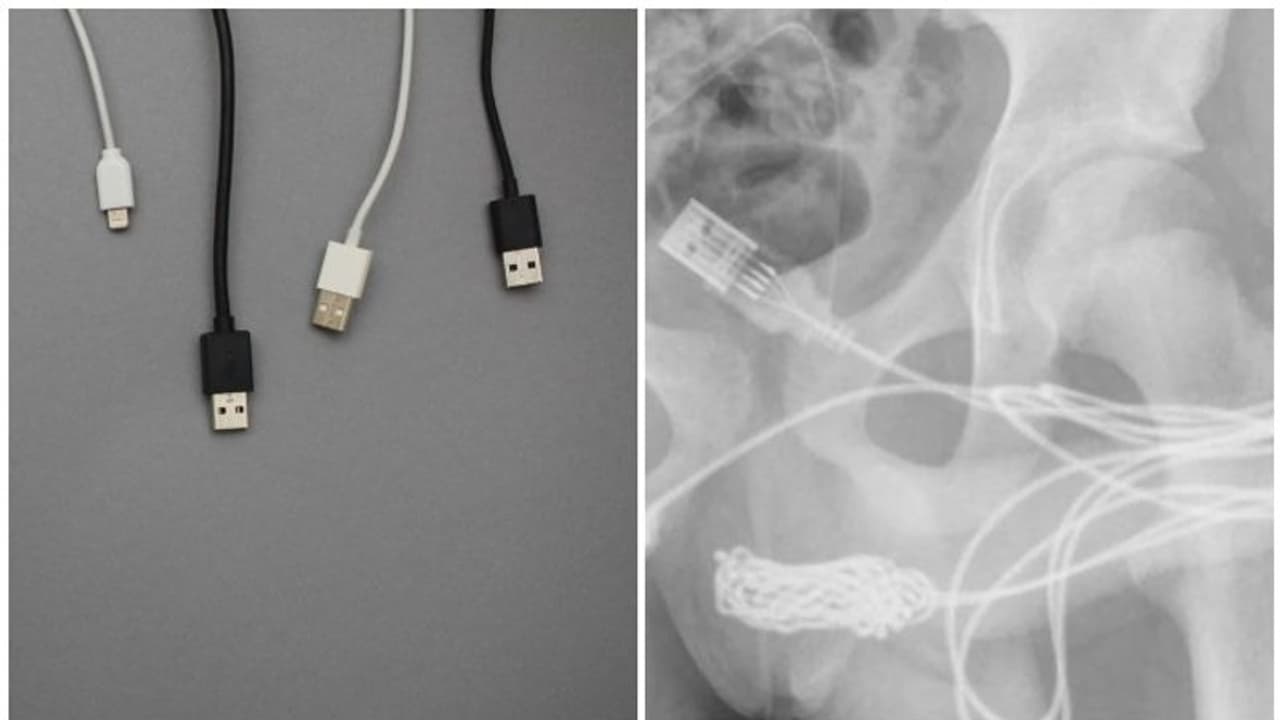

യുഎസ്ബി കേബിൾ (usb cable) ഉപയോഗിച്ച് ലിംഗത്തിന്റെ (penis) നീളം അളക്കാൻ ശ്രമിക്കുന്നതിനിടെ 15 വയസുകാരന്റെ ജനനേന്ദ്രിയത്തിൽ കേബിൾ കുടുങ്ങി. രക്ഷിതാക്കൾ കുട്ടിയെ ഉടൻ തന്നെ സമീപത്തുള്ള ആശുപത്രിയിൽ എത്തിച്ചു.

പരിശോധനയിൽ ലിംഗത്തിനുള്ളിൽ കേബിൾ കുടുങ്ങിയിരിക്കുന്നതായി കണ്ടെത്തുകയും ഉടൻ തന്നെ ഡോക്ടർമാർ കേബിൾ പുറത്തെടുക്കാൻ ശ്രമിച്ചെങ്കിലും പരാജയപ്പെട്ടു. കൂടുതൽ ചികിത്സയ്ക്കായി കുട്ടിയെ ലണ്ടൻ യൂണിവേഴ്സിറ്റി കോളേജ് ആശുപത്രിയിലേക്ക് മാറ്റി.

തുടർന്ന് ഡോക്ടർമാർ ഉടൻ തന്നെ ശസ്ത്രക്രിയ ചെയ്യുകയായിരുന്നു. ജനനേന്ദ്രിയത്തിനും മലദ്വാരത്തിനും ഇടയിലുള്ള ബൾബോസ്പോംഗിയോസസ് പേശികളിലേക്ക് നീളത്തിൽ മുറിച്ചു. ശസ്ത്രക്രിയയിലൂടെ ലിംഗത്തിനുള്ളിൽ കുടുങ്ങി കിടന്ന കേബിൾ നീക്കം ചെയ്തുവെന്ന് ഡെയ്ലി മെയില് റിപ്പോർട്ട് ചെയ്തു.